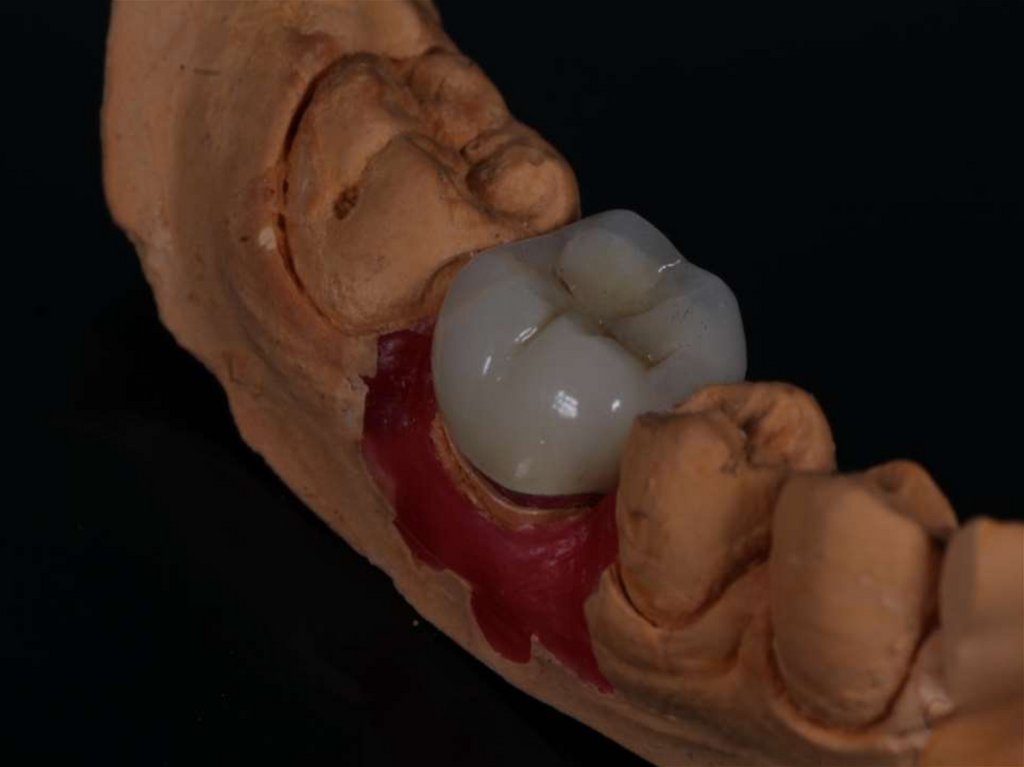

Методики пломбирования корневых каналов

Материалы для пломбирования корневых каналов

Пломбирование корневых каналов зуба